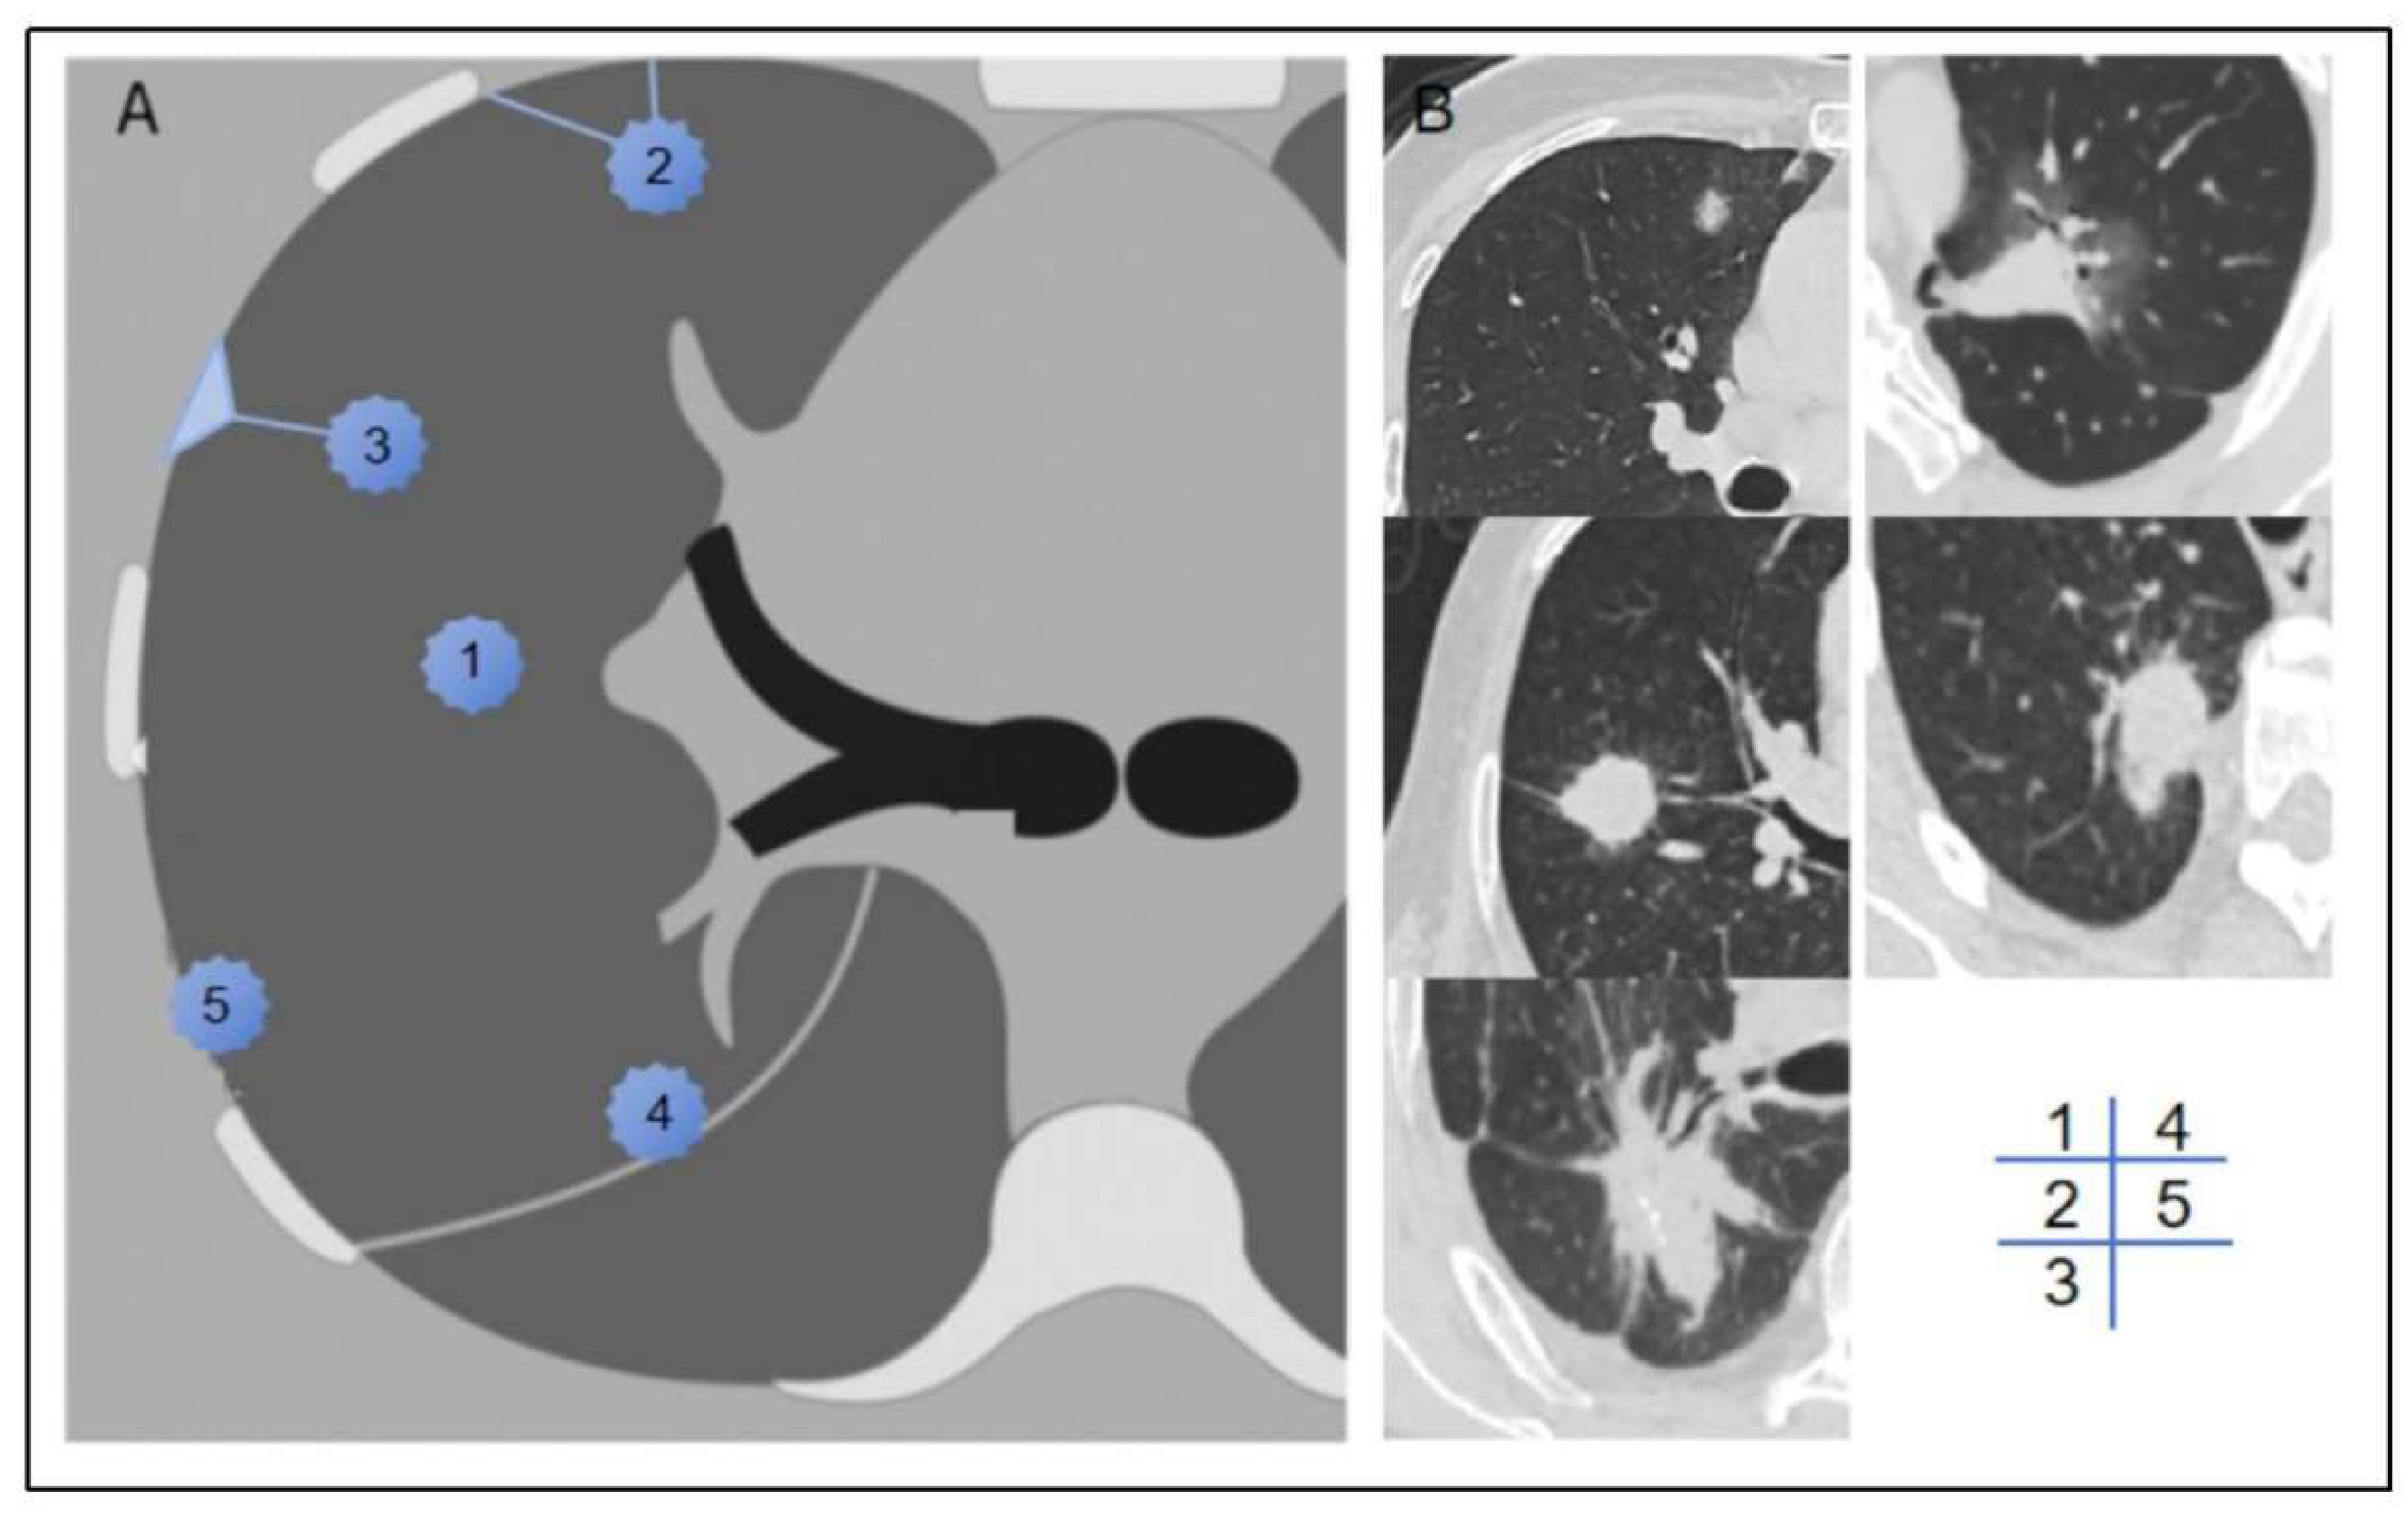

We documented the demographic information, laboratory test results, and tumor marker levels for all enrolled patients. These data included variables such as gender, age, BMI, smoking history, neutrophil-to-lymphocyte ratio (NLR), platelet-to-lymphocyte ratio (PLR), lymphocyte-to-monocyte ratio (LMR), prothrombin time (PT), activated partial thromboplastin time (APTT), fibrinogen (FIB), D-dimer levels, and a panel of tumor markers, including carcinoembryonic antigen (CEA), carbohydrate antigen 125 (CA125), carbohydrate antigen 19-9 (CA19-9), human CYFRA21-1 antigen (CYFRA21-1), and neuron-specific enolase (NSE). Preoperative CT scans were utilized to assess the patients' clinical T stage (cT stage) and to evaluate the relationship between the tumor and pleura. Based on previous studies [12], we classified the tumor-pleura relationship into five distinct types, ranging from tumors confined to the lung parenchyma to those directly contacting with the parietal pleura (as illustrated in Figure 2).

Figure 2. Schematic and example of type 1-5 tumour-pleura relationships. Type 1,the tumor was located inner the lung unrelated to the pleura. Type 2,the tumour was not in contact with the pleura, and one or more linear or striated pleural tags were visible. Type 3, the tumour was not in contact with the pleura, and one or more linear or striated pleural tags with soft tissue component at the pleural end were visible. Type 4, the tumour was in contact with the interlobar pleura. Type 5,the tumour was in contact with the parietal pleura.

Zhang et al.[12] previously categorized the tumor-pleura relationship into four types to predict predict occult lymphatic metastasis in clinical stage IA lung adenocarcinoma. In our study, we further refined this classification by distinguishing between tumor in contact with the visceral pleura and those in contact with the parietal pleura. Univariate analysis revealed that tumors located closer to the lung center had a lower probability of pleural metastasis, consistent with conventional understanding. Conversely, tumors adjacent to the parieal pleura exhibited a higher likelihood of metastasis compared to those near the interlobar pleura, likely due to the larger contact area and the denser lymphatic network beneath the parietal pleura. These findings underscore the importance of tumor location in predicting metastasis potential and provide a more nuanced framework for risk stratification.